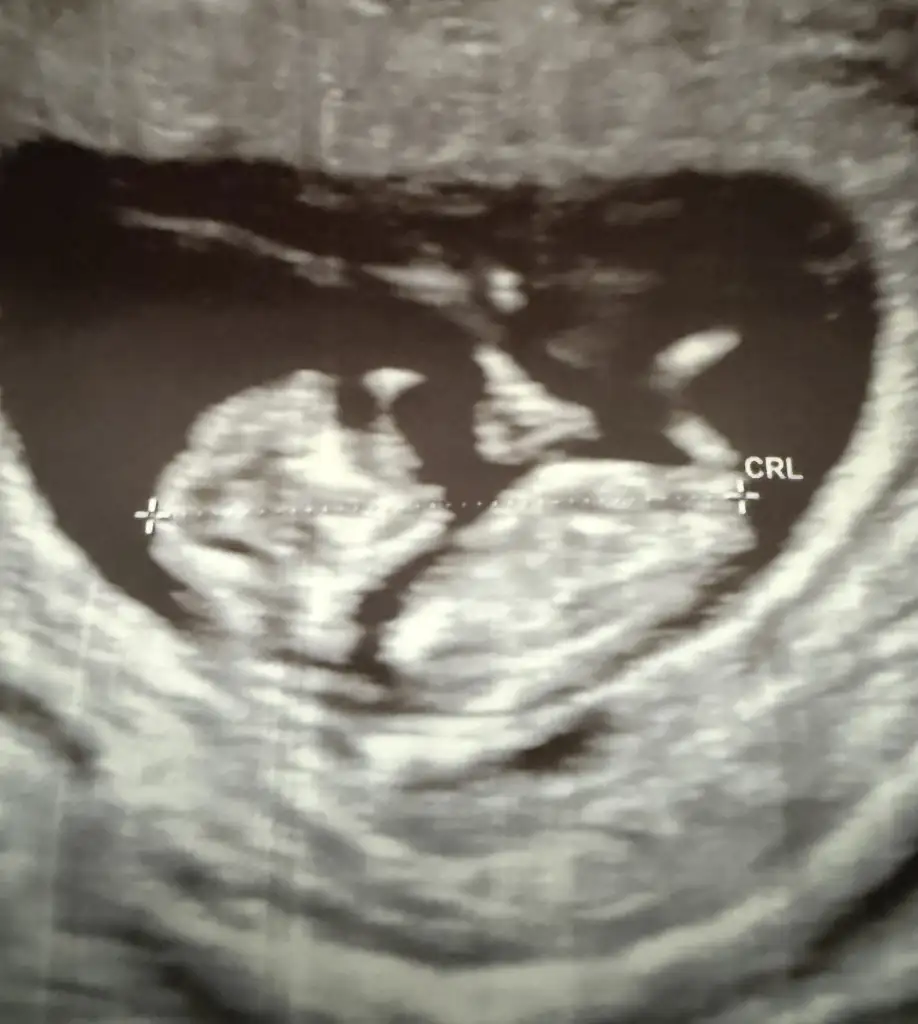

Erkek mi? :)kızlar bugün doktor kontrolüne gittim 10+3 üz ama 11 çıktı elhamdulillah gelişimi güzel dedi bide şaşırdım cinsiyeti söyledi tahmin bile değil direk bu dedi sordum bacak arasından mı yoksa kemik yapısından mı anladınız ikiside dedi hem bacak arası belli hem kemik yapısı foto arıcam tahminleri alayımEki Görüntüle 3670542